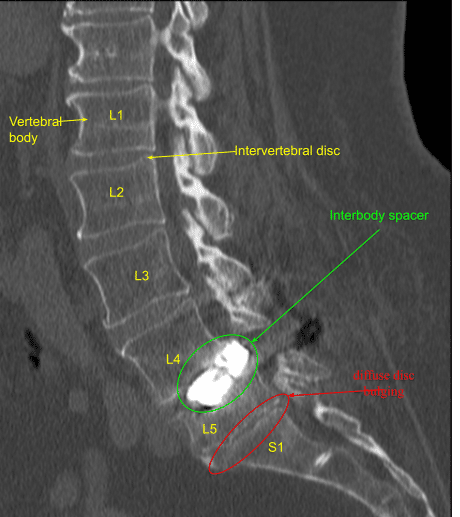

A patient presented to our clinic with a history of at least two other lumbar spine surgeries with recurrence of severe low back pain, inability to ambulate and imaging showing severe adjacent segment stenosis as well as hardware malfunction, mispositioning and pseudarthrosis.

Intraoperative CT scan was obtained. Data was transferred to the neuronavigation computer. Accuracy was verified. Stereotactic image-guided neuronavigation techniques were used to reposition and replace the new pedicle screw at L4 on the right side in a proper position.

Next, an intraoperative CT scan was obtained showing the correct position of all the screws. Next, we performed L3-4 laminectomy using Leksell rongeurs collecting autograft for morselization for arthrodesis, exposing hypertrophic ligamentum flavum which was retracted in a piecemeal fashion with Kerrison rongeurs.